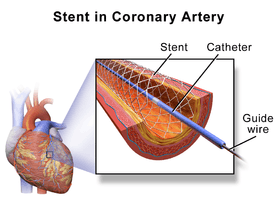

During PCI, a cardiologist feeds a deflated balloon or other device on a catheter from the inguinal femoral artery or radial artery up through blood vessels until they reach the site of blockage in the heart. X-ray imaging is used to guide the catheter threading. Angioplasty usually involves inflating a balloon to open the artery and allow blood flow. Stents or scaffolds may be placed at the site of the blockage to hold the artery open.

- If a stent was on the balloon, then it will be implanted (left behind) to support the new stretched open position of the artery from the inside.[21]